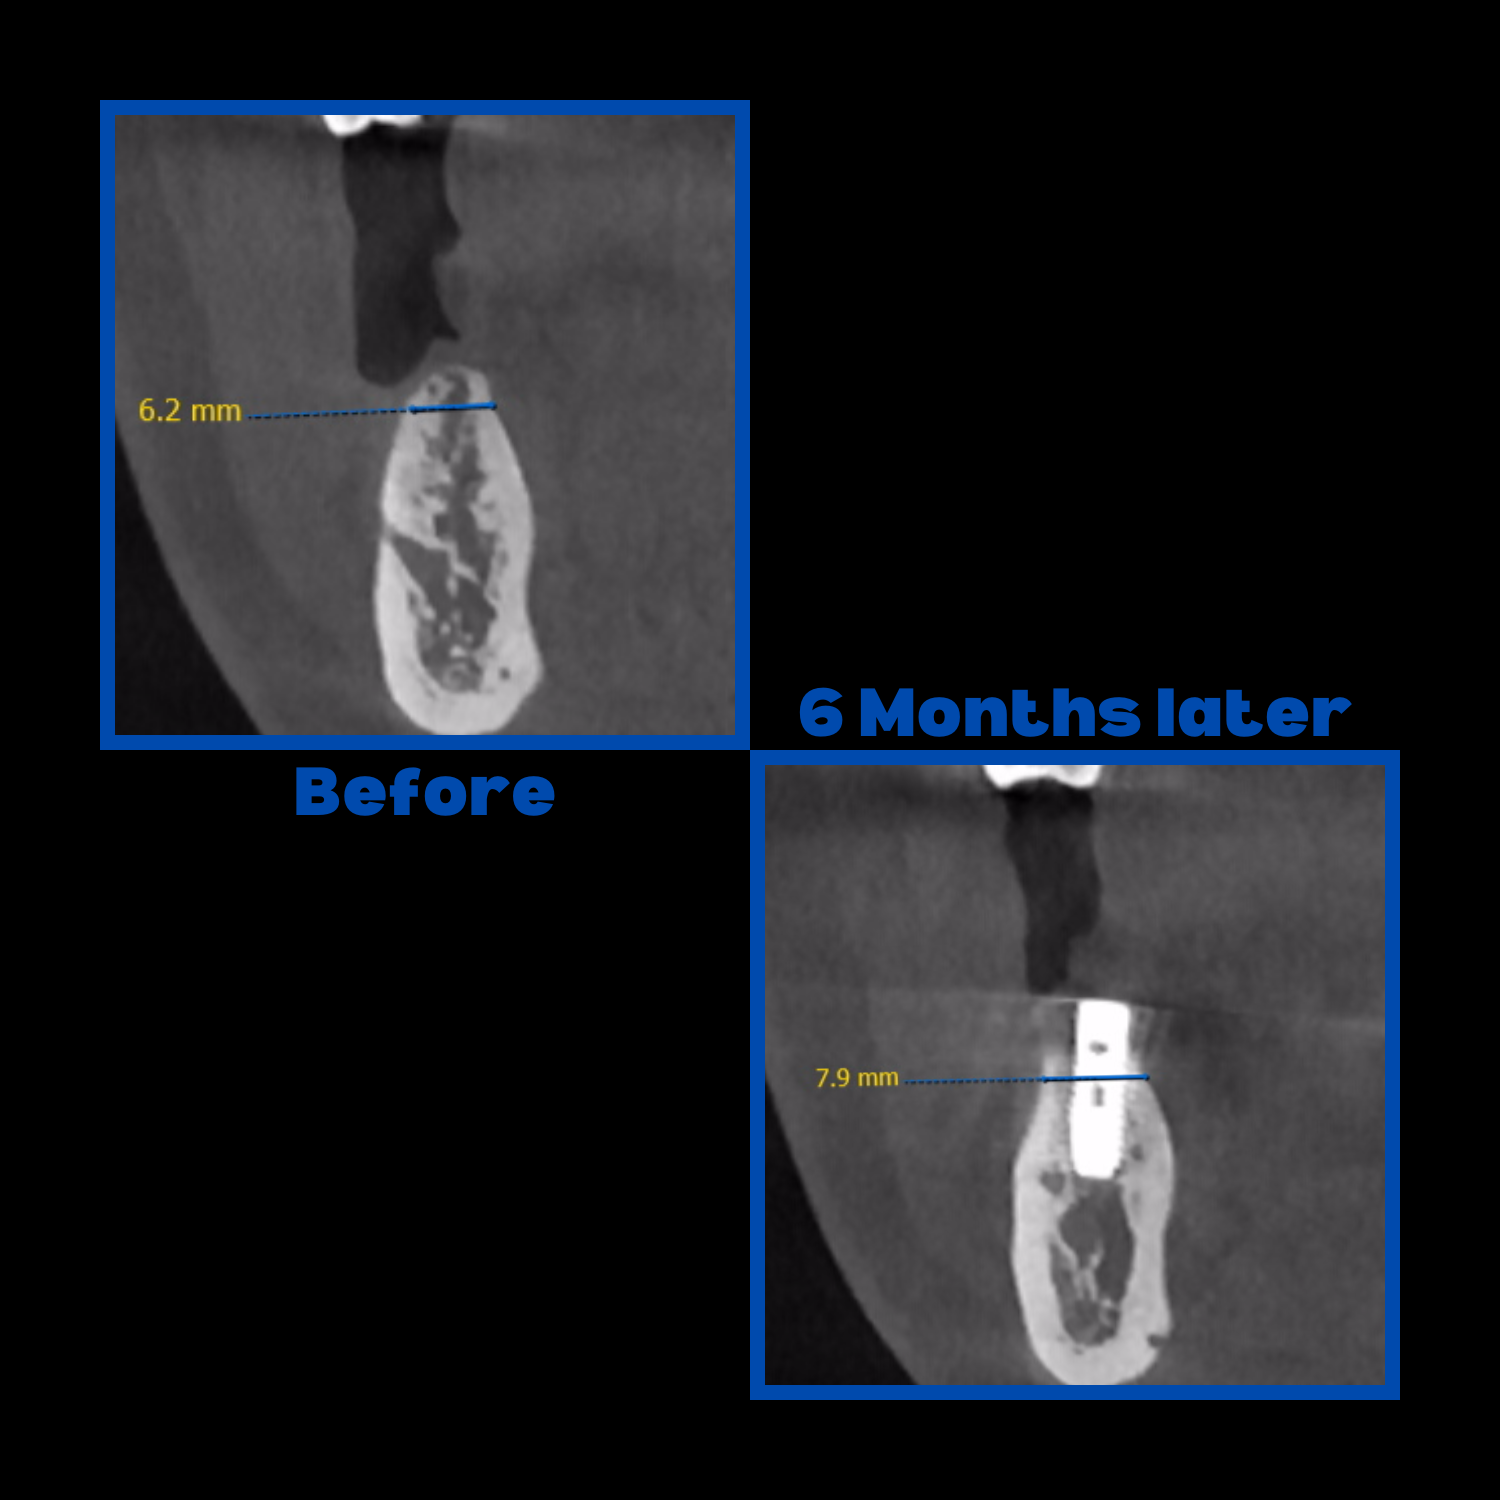

Diş çekiminin yıllar önce yapılmış olmasına bağlı olarak ince kemik varlığında implant ve kemik grefti uygulandı.